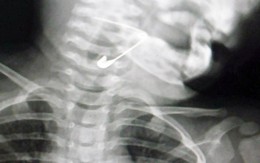

Lấy kim băng trong thực quản bé gái 18 tháng tuổi

TTO - Chiều 23-8, bác sĩ Nguyễn Thành Phương (trưởng khoa Tai - Mũi - Họng, Bệnh viện Đa khoa Vĩnh Đức, thị xã Điện Bàn, Quảng Nam) cho biết bệnh viện vừa lấy thành công một kim băng trong thực quản của một bé gái.